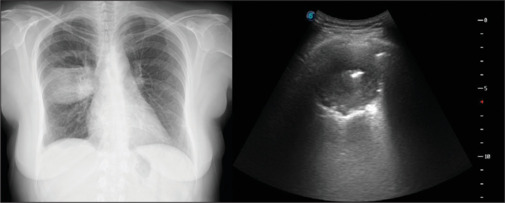

胸部超声(TUS)是一种长期建立的成像方式,在诊断许多胸膜实质疾病方面具有公认的有效性和可靠性。肺脓肿(LA)是一种以肺实质内液化性坏死和空化为特征的传染病,多见于免疫抑制患者或有多种危险因素的患者。它的治疗包括有效的抗生素治疗,在极少数情况下,引流或手术。在可行的情况下,从LA获取样本对于根据培养物中鉴定的病原体启动靶向治疗至关重要。在这个病例报告中,我们提出了一个44岁的女性患者住院的洛杉矶。脓肿通过超声显像,在超声引导下取样,并在持续的超声监测下成功处理。

Thoracic ultrasonography (TUS) is a long-established imaging modality with proven efficacy and reliability in the diagnosis of numerous pleuro-parenchymal diseases. Lung abscess (LA) is an infectious disease characterized by liquefactive necrosis and cavitation within the pulmonary parenchyma, typically occurring in immunosuppressed patients or those with various risk factors. Its treatment involves effective antibiotic therapy and, in rare cases, drainage or surgery. Obtaining a sample from the LA, when feasible, is crucial for initiating targeted therapy based on the pathogen identified in the culture. In this case report, we present a 44-year-old female patient hospitalized for an LA. The abscess was visualized via TUS, sampled under ultrasound guidance and successfully managed with ongoing ultrasonographic monitoring.